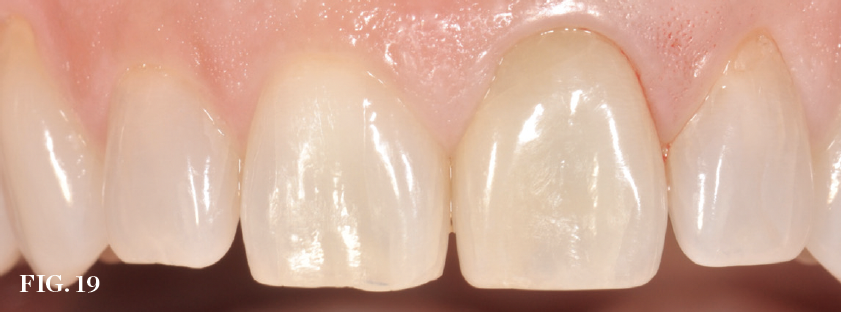

(19.) Preoperative view of a failing central incisor (tooth No. 9). Note the early recession occurring in the region.

Figure 19